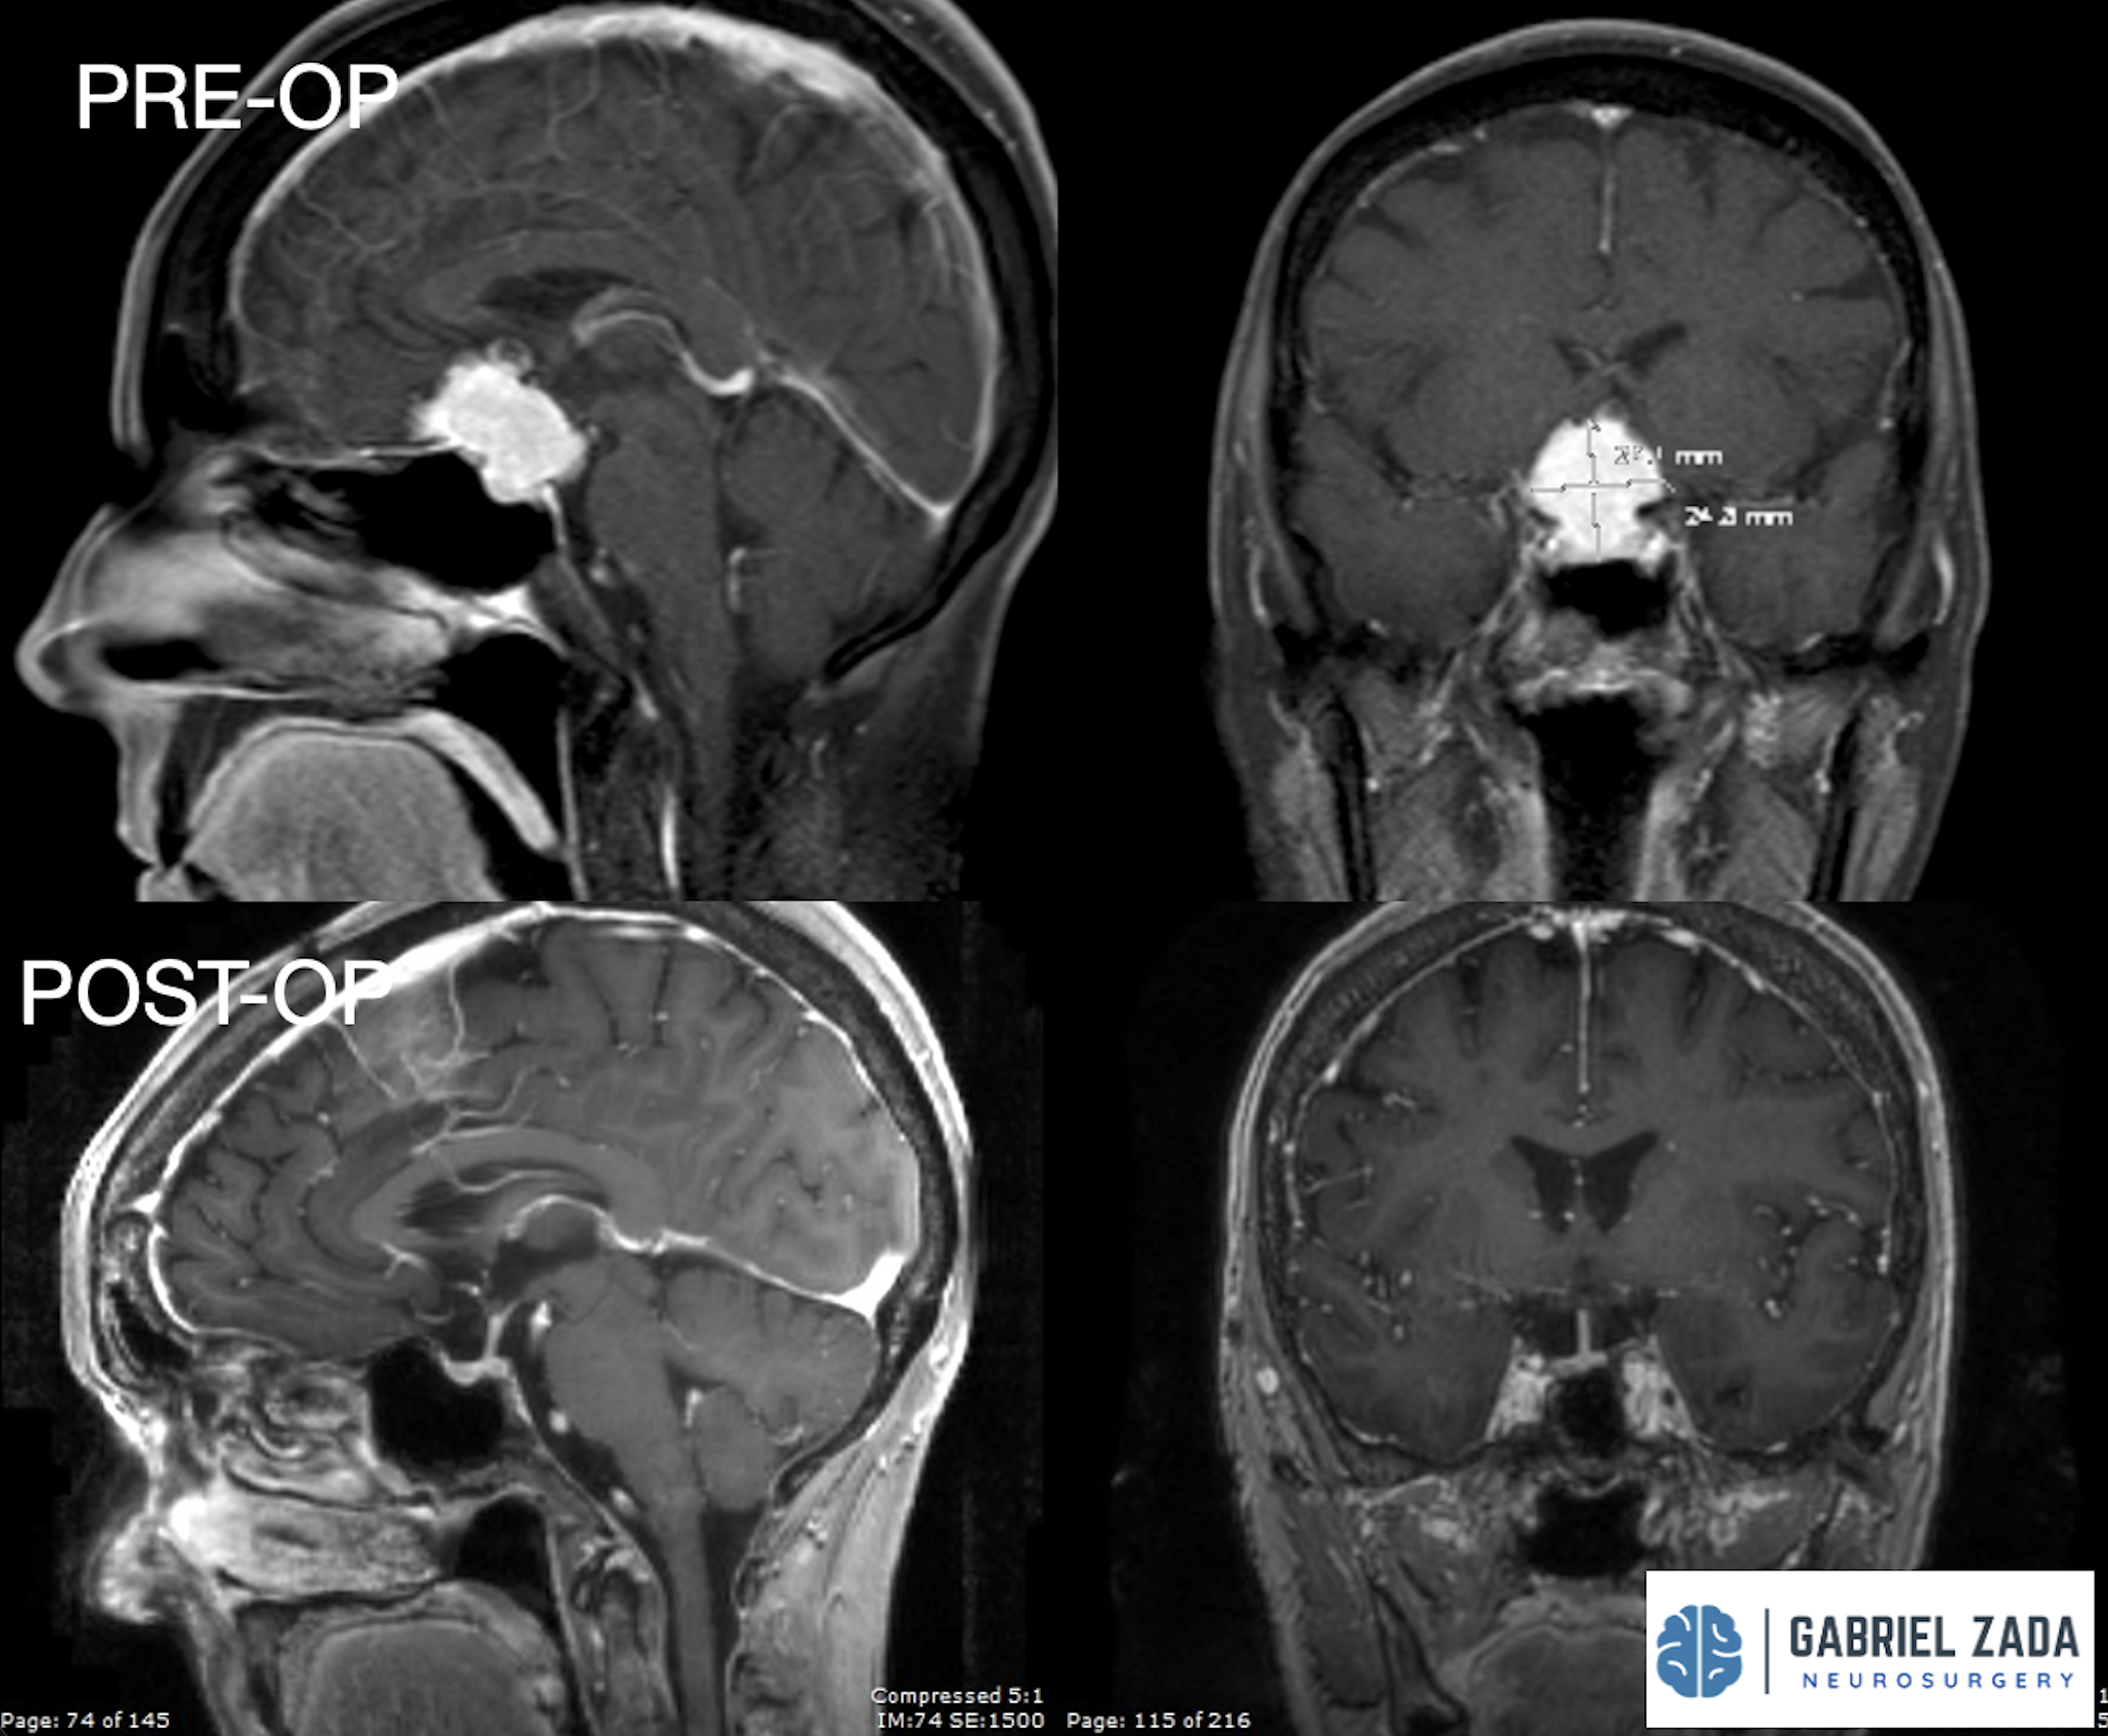

Explore this comprehensive gallery featuring pre‑ and post‑operative imaging of patients with skull‑base tumors treated by Gabriel Zada, MD, MS, FAANS, FACS. These cases highlight Dr. Zada’s expertise in advanced neurosurgical techniques and outcomes.

*Representative cases shown for educational purposes. All images de-identified. Individual results vary.